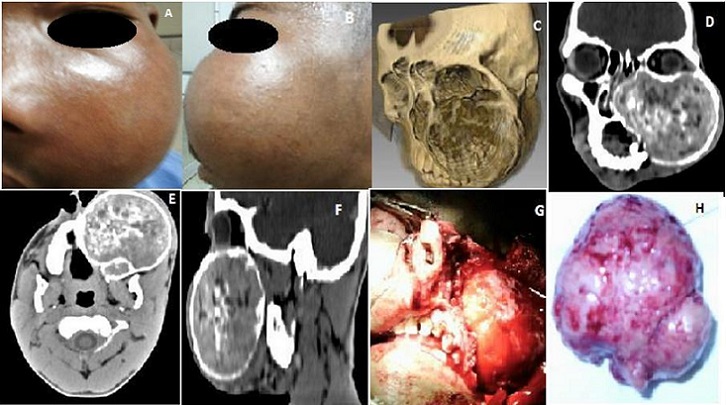

Les adénomes pléomorphes, retrouvés le plus souvent au niveau des glandes salivaires, sont localisés exceptionnellement dans un sinus de la face. Notre observation concerne un patient de genre masculin, âgé de 17 ans, qui a présenté depuis un an, du côté gauche, une obstruction nasale, une rhinorrhée muqueuse, une épistaxis, une douleur infra-orbitaire irradiant vers les dents maxillaires et un larmoiement. L'inspection a montré une hémiface fortement déformée par une tuméfaction lisse faisant huit centimètres de grand axe (A,B), de consistance dure à la palpation. La rhinoscopie antérieure a révélé dans la cavité nasale gauche une tumeur lisse, blanchâtre, non hémorragique, non infectée, refoulant le septum. L'examen des paires des nerfs crâniens a été sans particularités. Un examen du fond d'œil et du champ visuel a été dans les limites de la normale. Les aires ganglionnaires cervicales ont été libres. Un examen tomodensitométrique du massif facial, avec et sans injection de produit de contraste, en reconstruction tridimensionnelle (C), en coupes coronales, axiales et sagittales (D,E,F), a objectivé une masse refoulant sans les lyser les structures osseuses et cartilagineuses avoisinantes (toit de l'ethmoïde, parois orbitaires, voûte palatine, septum nasal). Un prélèvement tumoral suivi d'un examen anatomopathologique a confirmé le diagnostic d'adénome pléomorphe. Une chirurgie d'exérèse a été menée par voie paralatéronasale (G), permettant d'enlever la tumeur en monobloc (H). Les suites opératoires ont été bonnes, les signes fonctionnels se sont progressivement amendés. Il n'y a pas eu de récidive tumorale six mois après l'intervention.